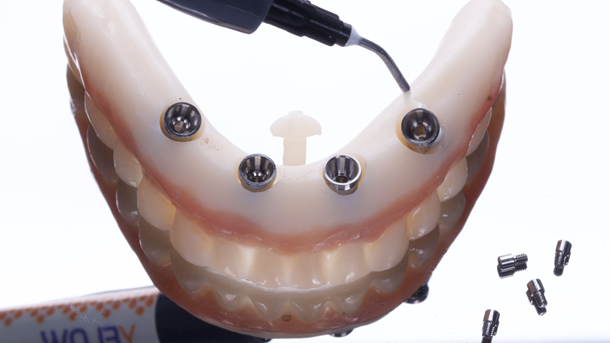

Os arquivos foram enviados para a empresa Raio 3D (Porto Velho – RO) para criação de uma guia empilhável; consistia em três partes que são mencionadas na discussão; e impressão da prótese provisória em resina através do processo de estereolitografia. A base da guia tomográfica e personalizada foi comparada e o exame clínico não mostrou sinais de desalinhamento ou pressão em qualquer área.

O guia foi fixado após estabilização em oclusão com a prótese superior. Após a retirada do guia de oclusão, foi fixada a guia de fresagem e instalação dos implantes, que foram instalados com torques superiores a 32N, o que permitiu a captura imediata da prótese provisória através do pilar de titânio e resina de fluxo.